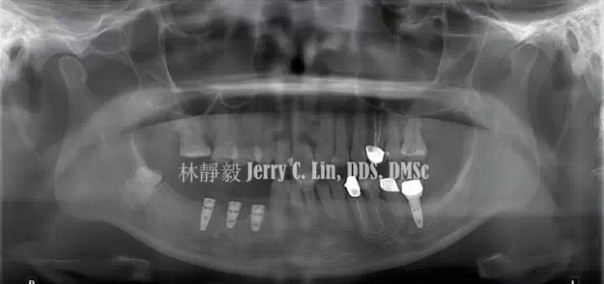

嚴(yán)重種植體周圍炎的處理(二)——林靜毅醫(yī)師